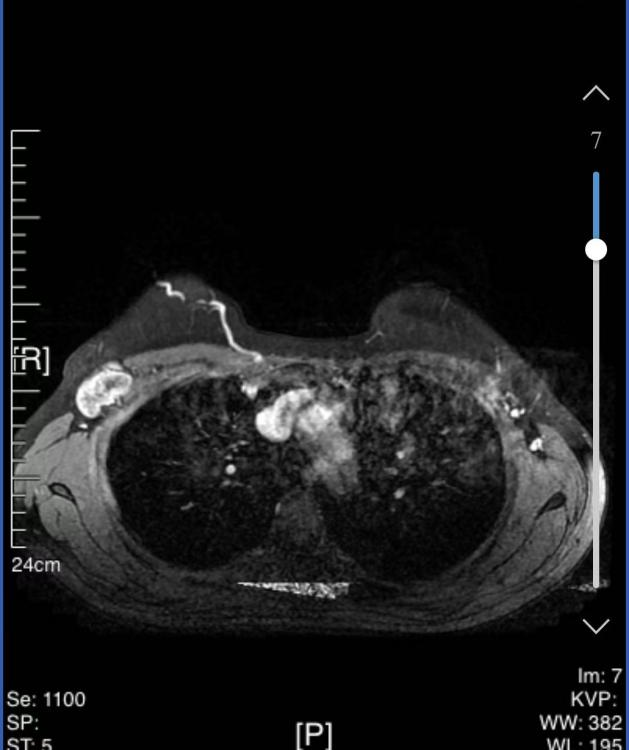

• 乳腺核磁共振(MRI):

1、右乳外侧象限见T2WI稍高信号肿物,大小约31mm*25mm*33mm,形态不规则,边缘分叶;内部强不均匀,TIC曲线初始呈快速强化,延迟期呈平台型;DWI呈高信号,ADC值为0.000811mm2/s。右腋窝见肿大淋巴结。

MRI提示:右乳外侧象限肿块及多处非肿块样强化,BI-RADS 5类;右腋窝淋巴结肿大。

图3 乳腺MRI结果(2024-03-04)